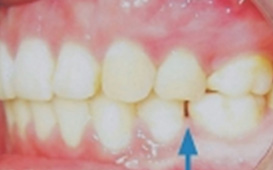

智慧齒萌發時常推擠前面牙齒,造成前面牙齒不正常之移動

請注意下列事項:

◎ 請勿在智齒尚未萌發完成之前,輕易放棄維護器之使用。

◎ 如您在智齒萌發前未遵循醫囑,主動停止使用維護器,則您應密切觀察牙齒是否有任何不良變化。如發現異常牙齒變動,煩請您在變化初期即時告知醫師;延遲告知醫師,會導致醫師已無法用一般簡易方式處理與修復,而可能導致不必要之再次治療與負擔治療費用。